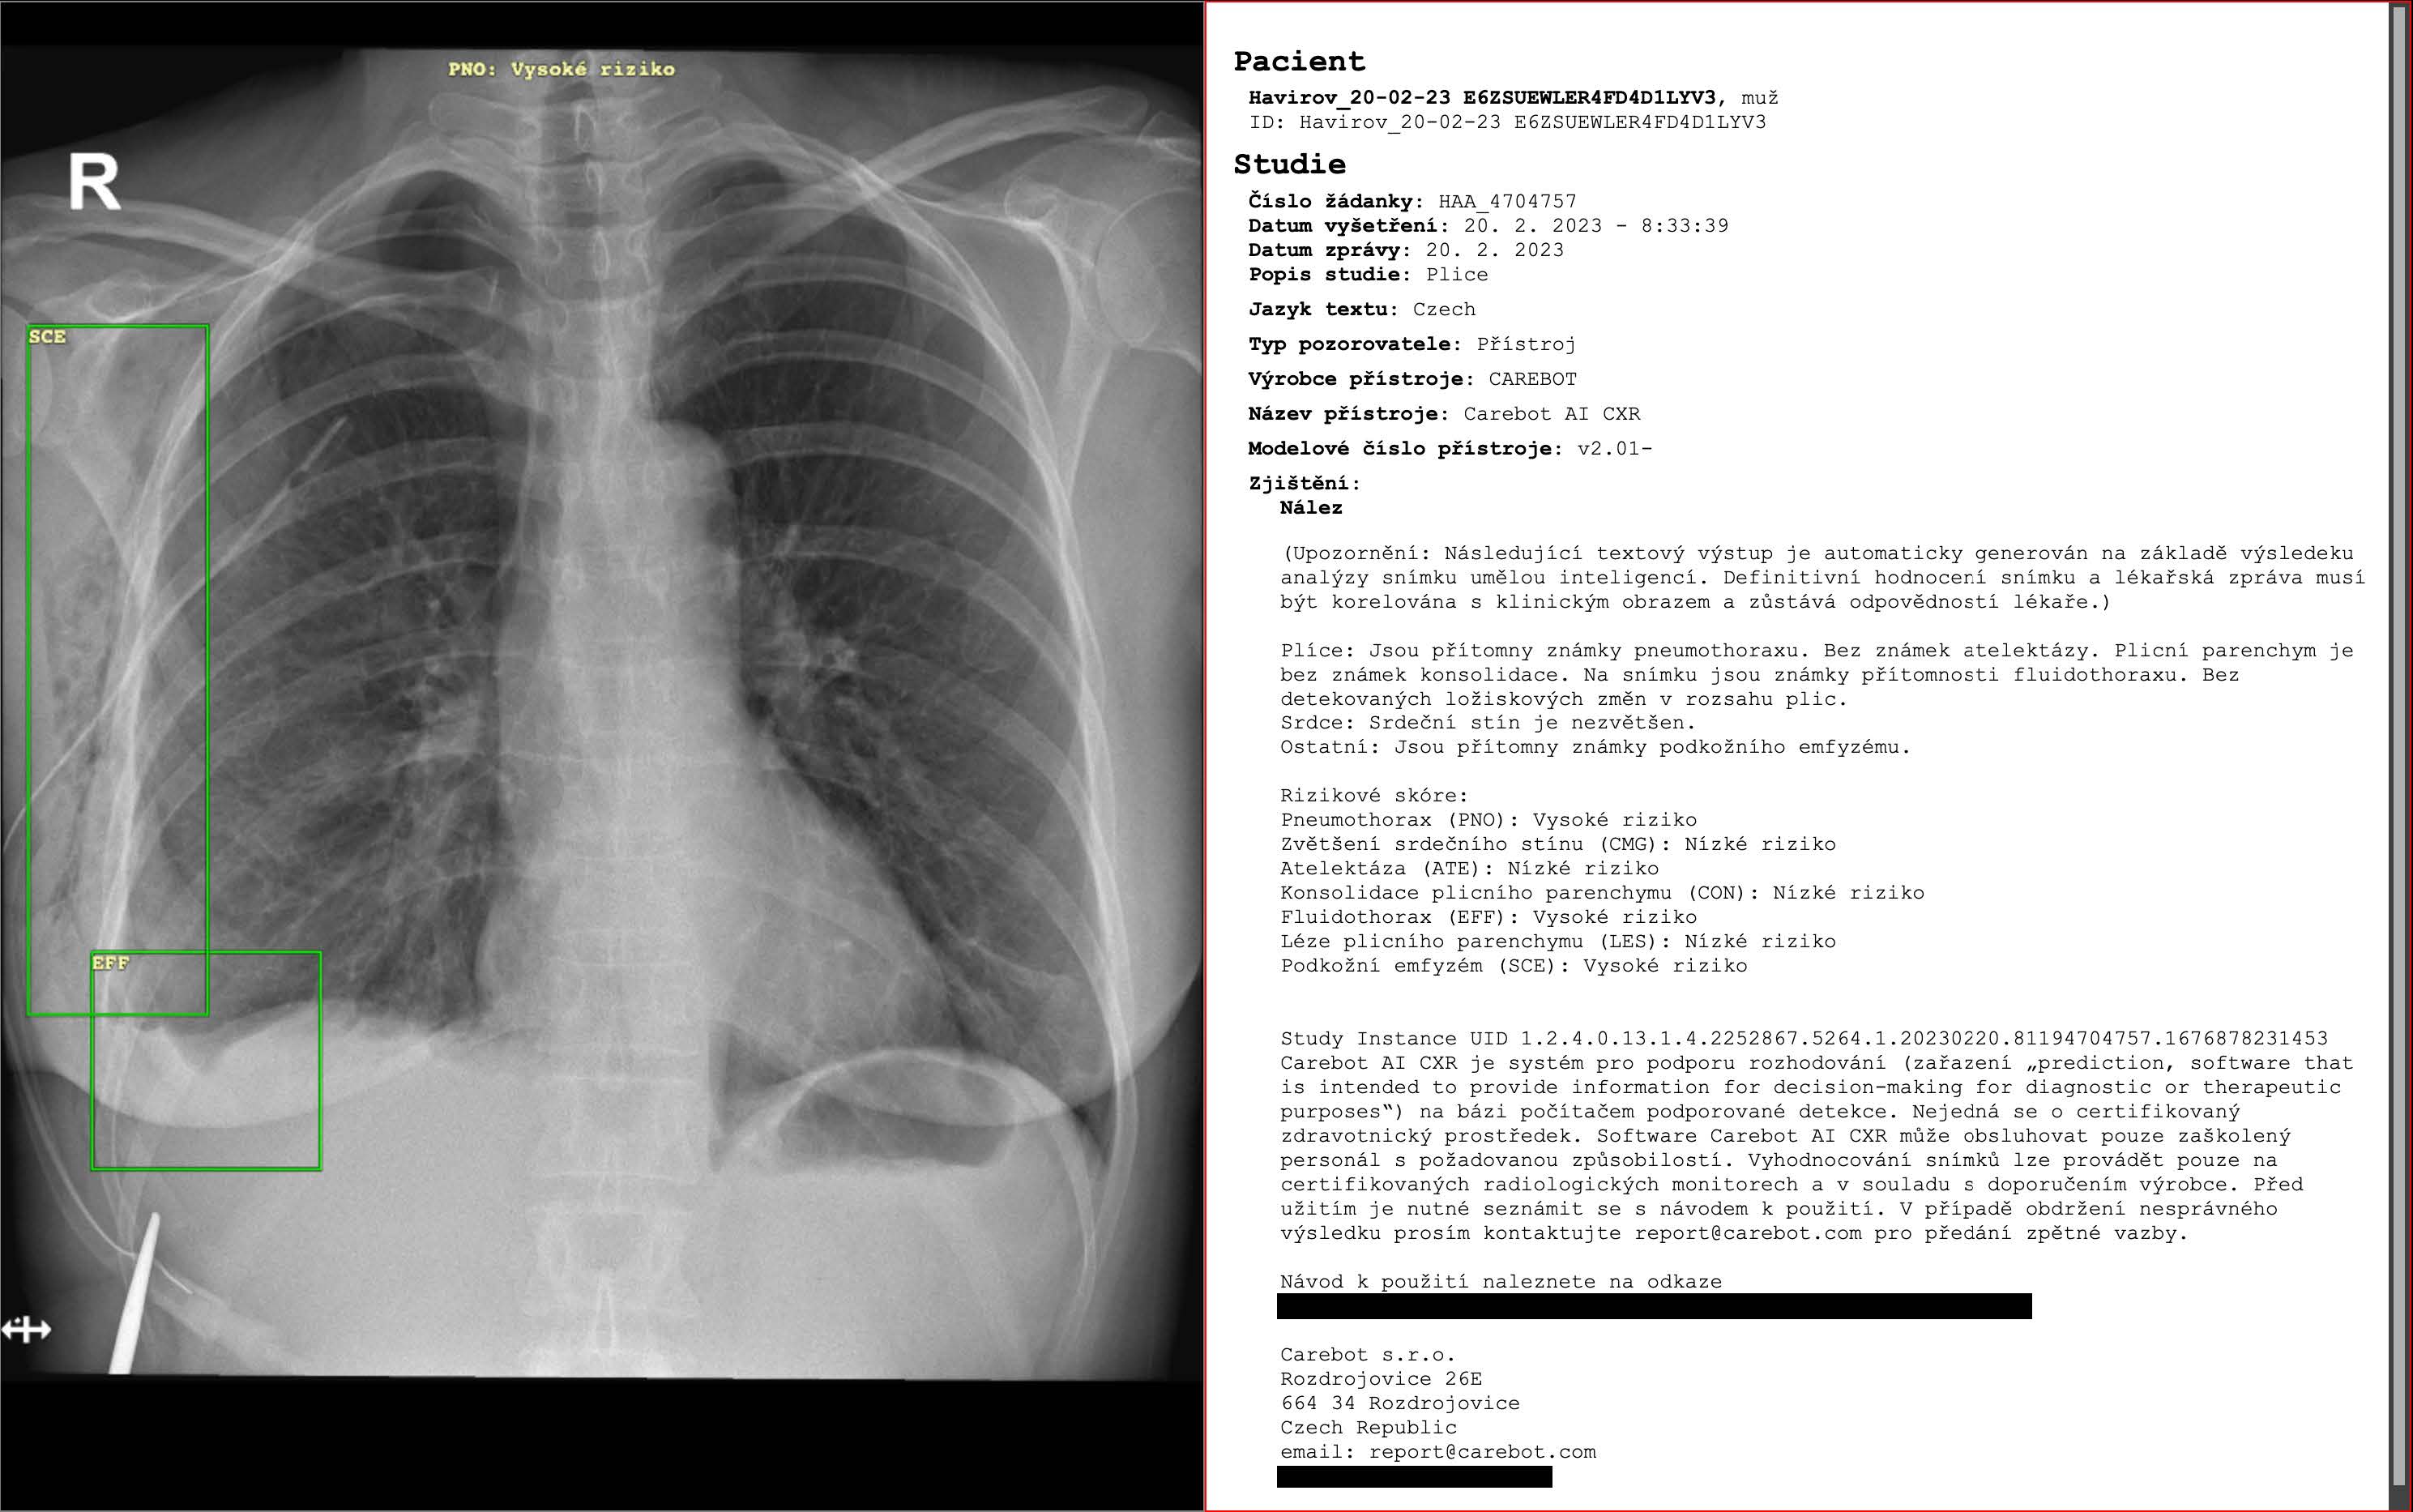

Evaluating Artificial Intelligence for Chest X-ray Analysis in a Low-Prevalence

Rentgen hrudníku (CXR) se často používá v ambulantní péči, kde jsou klinicky relevantní abnormality vzácné a užitečnost umělé inteligence...

AI-Assisted Chest X-ray Reading Improves Sensitivity

Rostoucí poptávka po rentgenovém vyšetření hrudníku ve zdravotnictví, kombinovaná s nedostatkem radiologů a rostoucím pracovním zatížením...